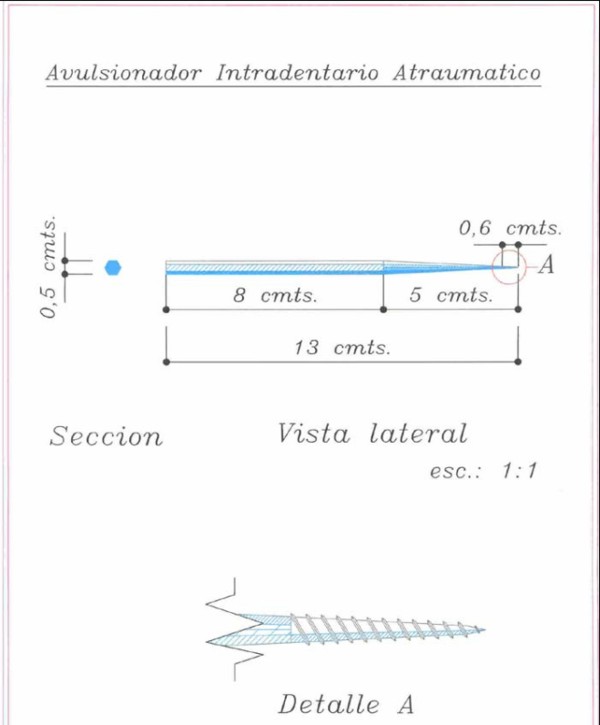

Las extracciones dentarias o EXODONCIAS, son habitualmente realizadas mediante la utilización de instrumentos denominados FÓRCEPS, los que instalados en el cuello de la pieza dentaria a extraer, son movidos de manera oscilante en el eje del diente, lográndose después de un corto período de tiempo, quitar al mismo de la cavidad ósea que lo aloja, en una operación que se denomina LUXACIÓN o AVULSIÓN. FÓRCEPS EN BOCA Esta AVULSIÓN, se produce debido a que el hueso es elástico. Sin embargo , gran parte de las veces esa elasticidad no es suficiente y se parte o rompe la «corteza ósea» que rodea al diente, en su región más cercana a la «zona cortante» del mismo.Esa ruptura o fractura, es favorecida por el uso de los Fórceps, dado que sus «mordientes» se sitúan muy cerca de del hueso. .FÓRCEPS ROMPIENDO LA TABLA TABLA ROTA La idea de crear un instrumento que impida dicha fractura, se basa en la certeza de que cuanto más adentro del diente, y cuanto más cerca de la punta del diente, se efectúe la fuerza de AVULSIÓN, menos posibilidades de fractura existirán por una simple cuestión de física básica: CUANTO MÁS LARGO SEA EL BRAZO DE POTENCIA DE UNA PALANCA, MENOS ACCIÓN TENDRA EL BRAZO DE RESISTENCIA….POR LO TANTO SERÁ NECESARIA MENOS POTENCIA PARA VENCER LA RESISTENCIA… O SEA, CON MOVIMIENTOS MAS DELICADOS , LOGRAREMOS EL MISMO EFECTO. ESQUEMA DE DIENTE MOSTRANDO LA ACCIÓN DE LAS FUERZAS DE UN FÓRCEPS. ESQUEMA DE DIENTE MOSTRANDO LA ACCIÓN DE FUERZAS DE UN AIDA Cuando la especialidad IMPLANTOLOGÍA, no se había desarrollado tal como ahora la conocemos, la fractura de esa «corteza ósea» denominada TABLA EXTERNA O INTERNA del PROCESO ALVEOLAR, carecía de importancia ya que la cicatrización se produce irremediablemente en ausencia de infecciones Sin embargo, a la luz de los conocimientos actuales, la preservación de dichas TABLAS, son de capital importancia para la realización de un IMPLANTE INMEDIATO(Implante colocado en el mismo acto quirúrgico que la extracción), y para el logro de su INTEGRACIÓN Y ESTÉTICA futura. Es por eso que exponemos ante las autoridades competentes, la idea de patentar un instrumento como el que denomino: AVULSIONADOR INTRADENTARIO ATRAUMÁTICO …cuyas características principales son: MATERIAL: ACERO QUIRÚRGICO 316 LONGITUD TOTAL:13 mm PUNTA ACTIVA: 6 mm FORMA DE PUNTA ACTIVA: HELICOIDAL DECRECIENTE DOS GROSORES DE PUNTA. INSTRUMENTO AD HOC Por acción de las espiras , el instrumento se fija en las paredes del canal dentario, produciendo un anclaje que permite la AVULSIÓN. CRESTA ÓSEA COMPLETAMENTE CONSERVADA

DIBUJO TÉCNICO DEL INSTRUMENTO